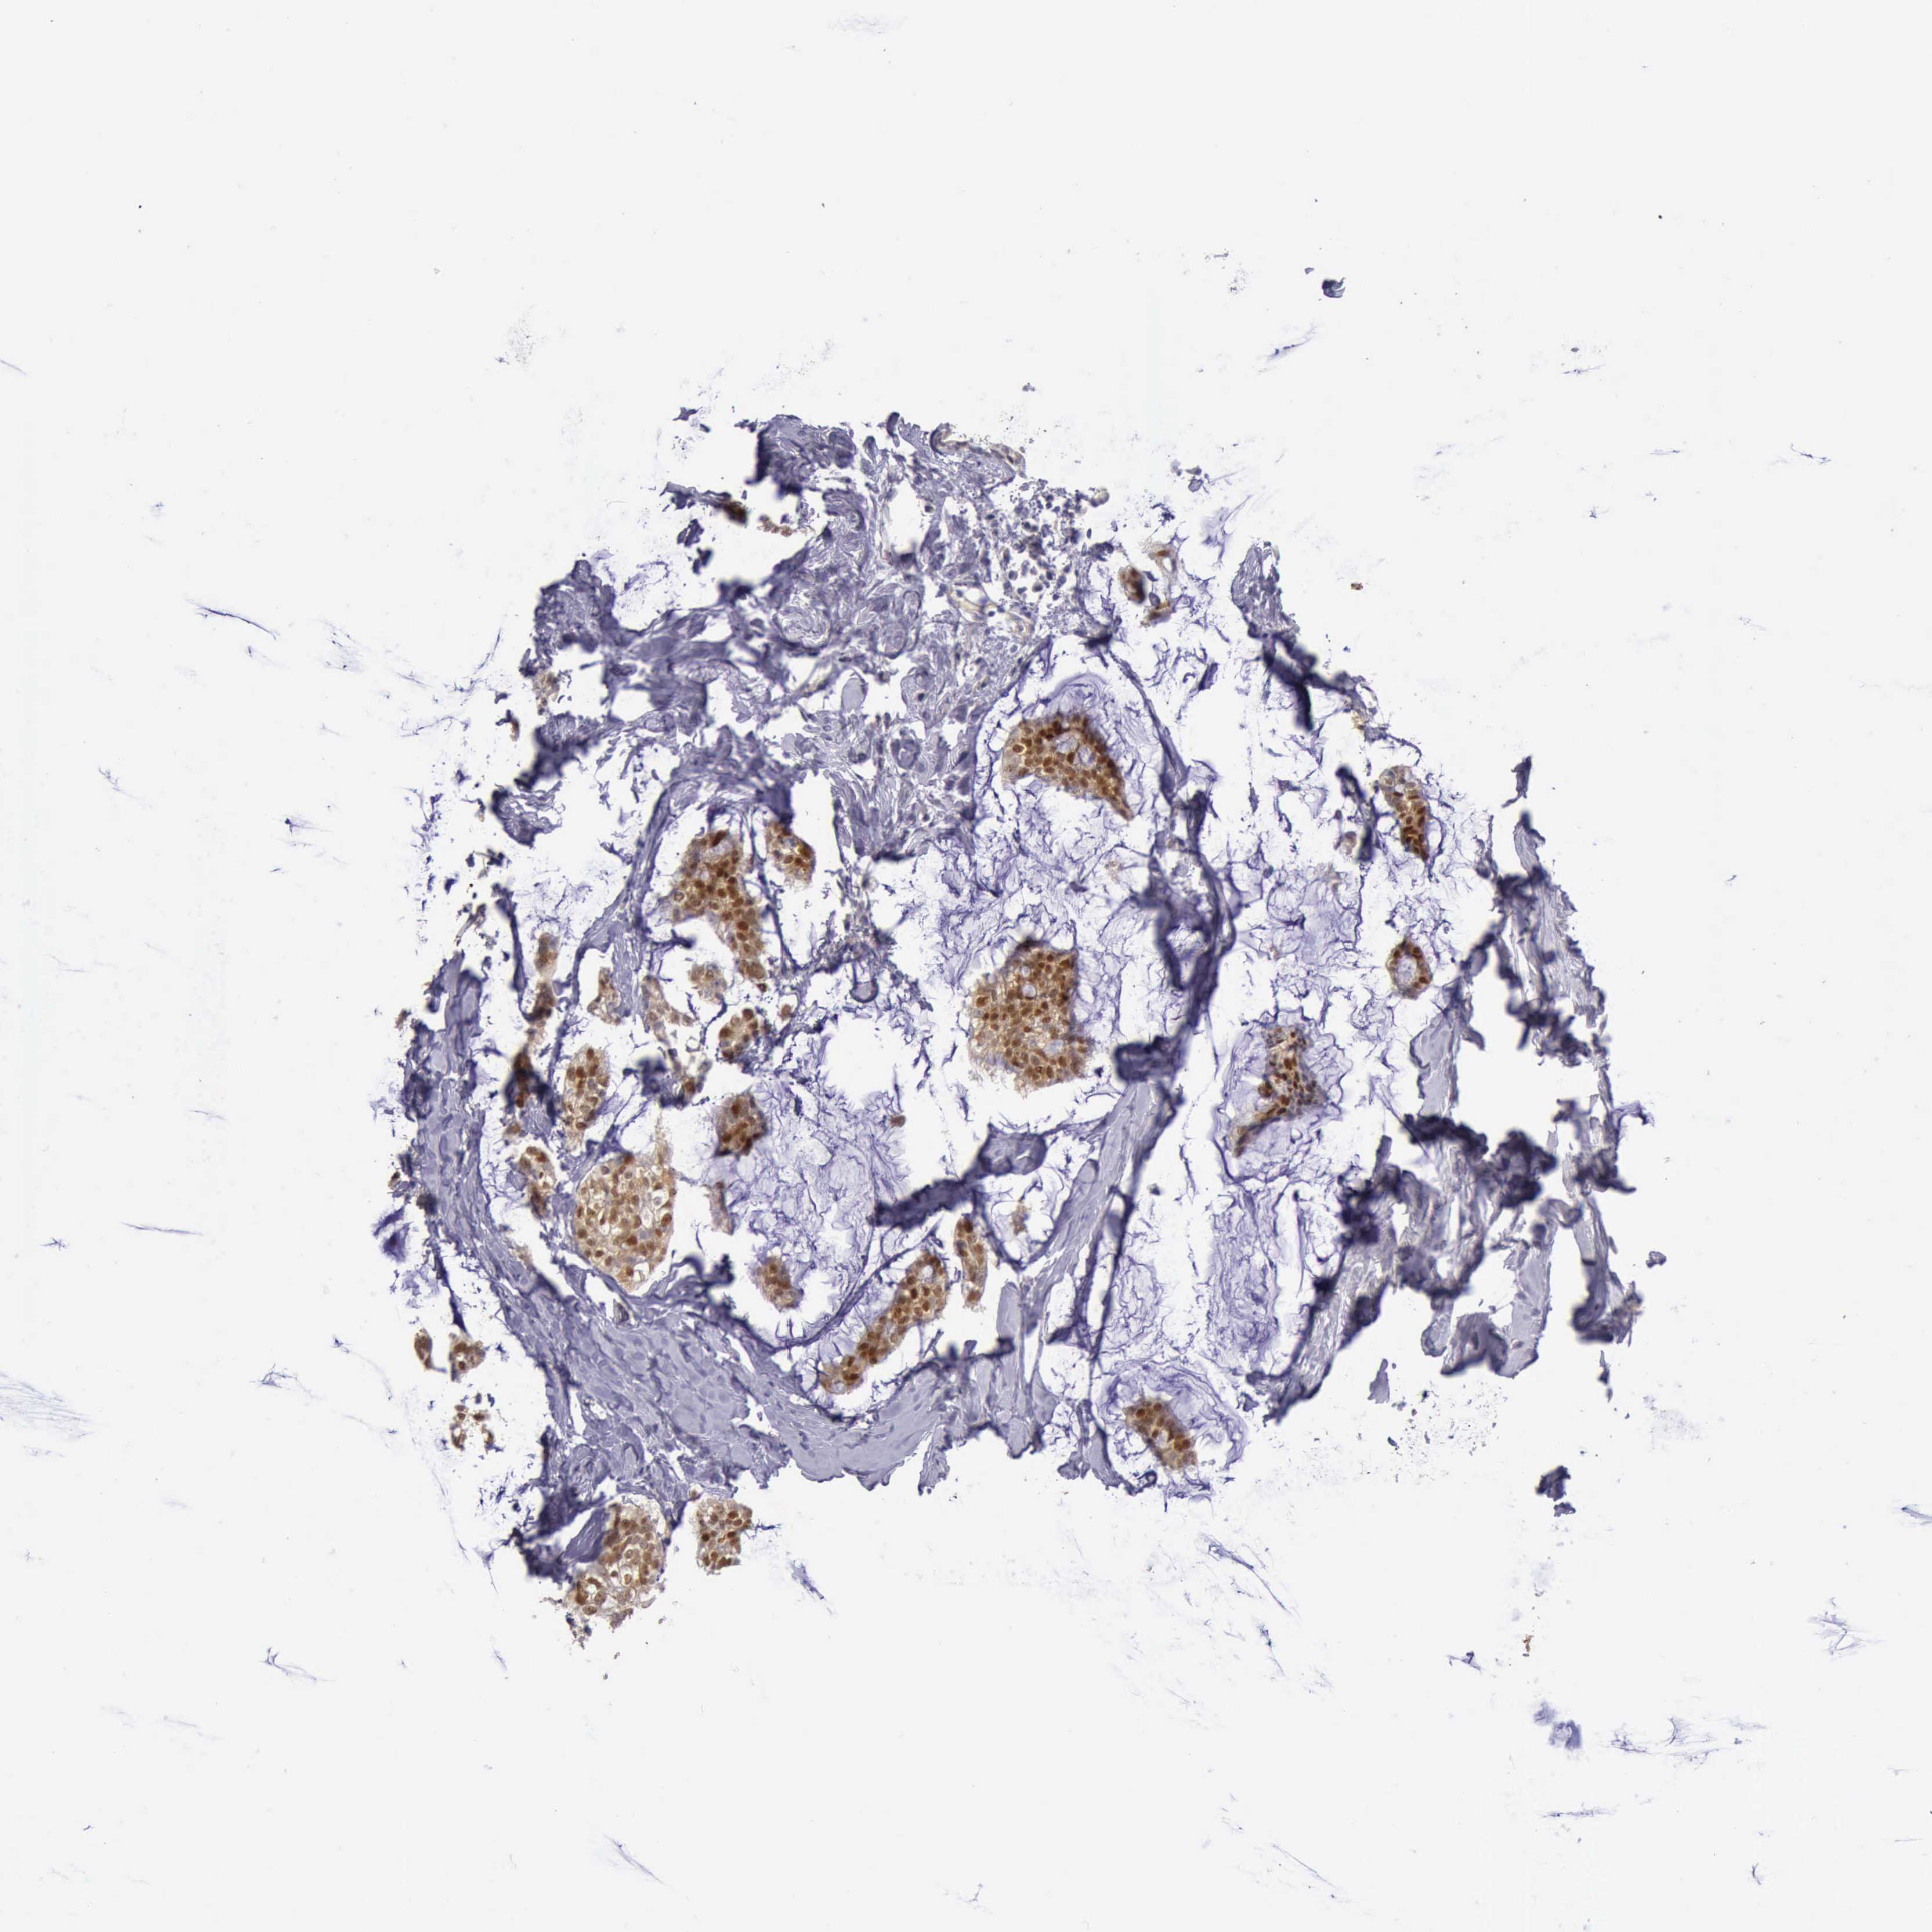

BRCA TCGA BRCA VALIDATION PROTEIN EXPRESSION